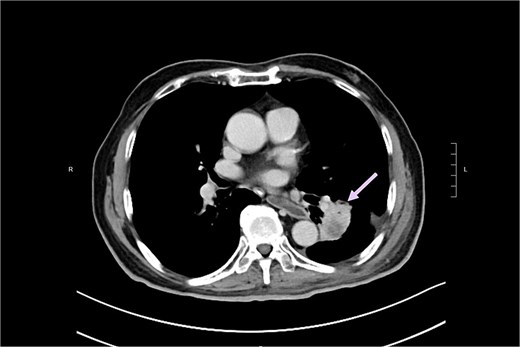

The patient was noted to have rising CEA up to 17ug/L at a time over 2 years after operation. PET CT showed a new 2.3 cm hypermetabolic lesion at lower lobe of left lung but no intra-abdominal recurrence (Fig. 7). Biopsy of lung lesion revealed mucinous adenocarcinoma, which could be lung primary or metastatic ICC. As the patient was not a candidate for lung resection, he received stereotactic body radiotherapy (SBRT) for the lung tumor. CEA gradually returned to normal afterwards and repeated CT revealed post-radiation change only at site of tumor (Fig. 8). The patient remained well ˃5 years since initial operation without evidence of further recurrent disease.